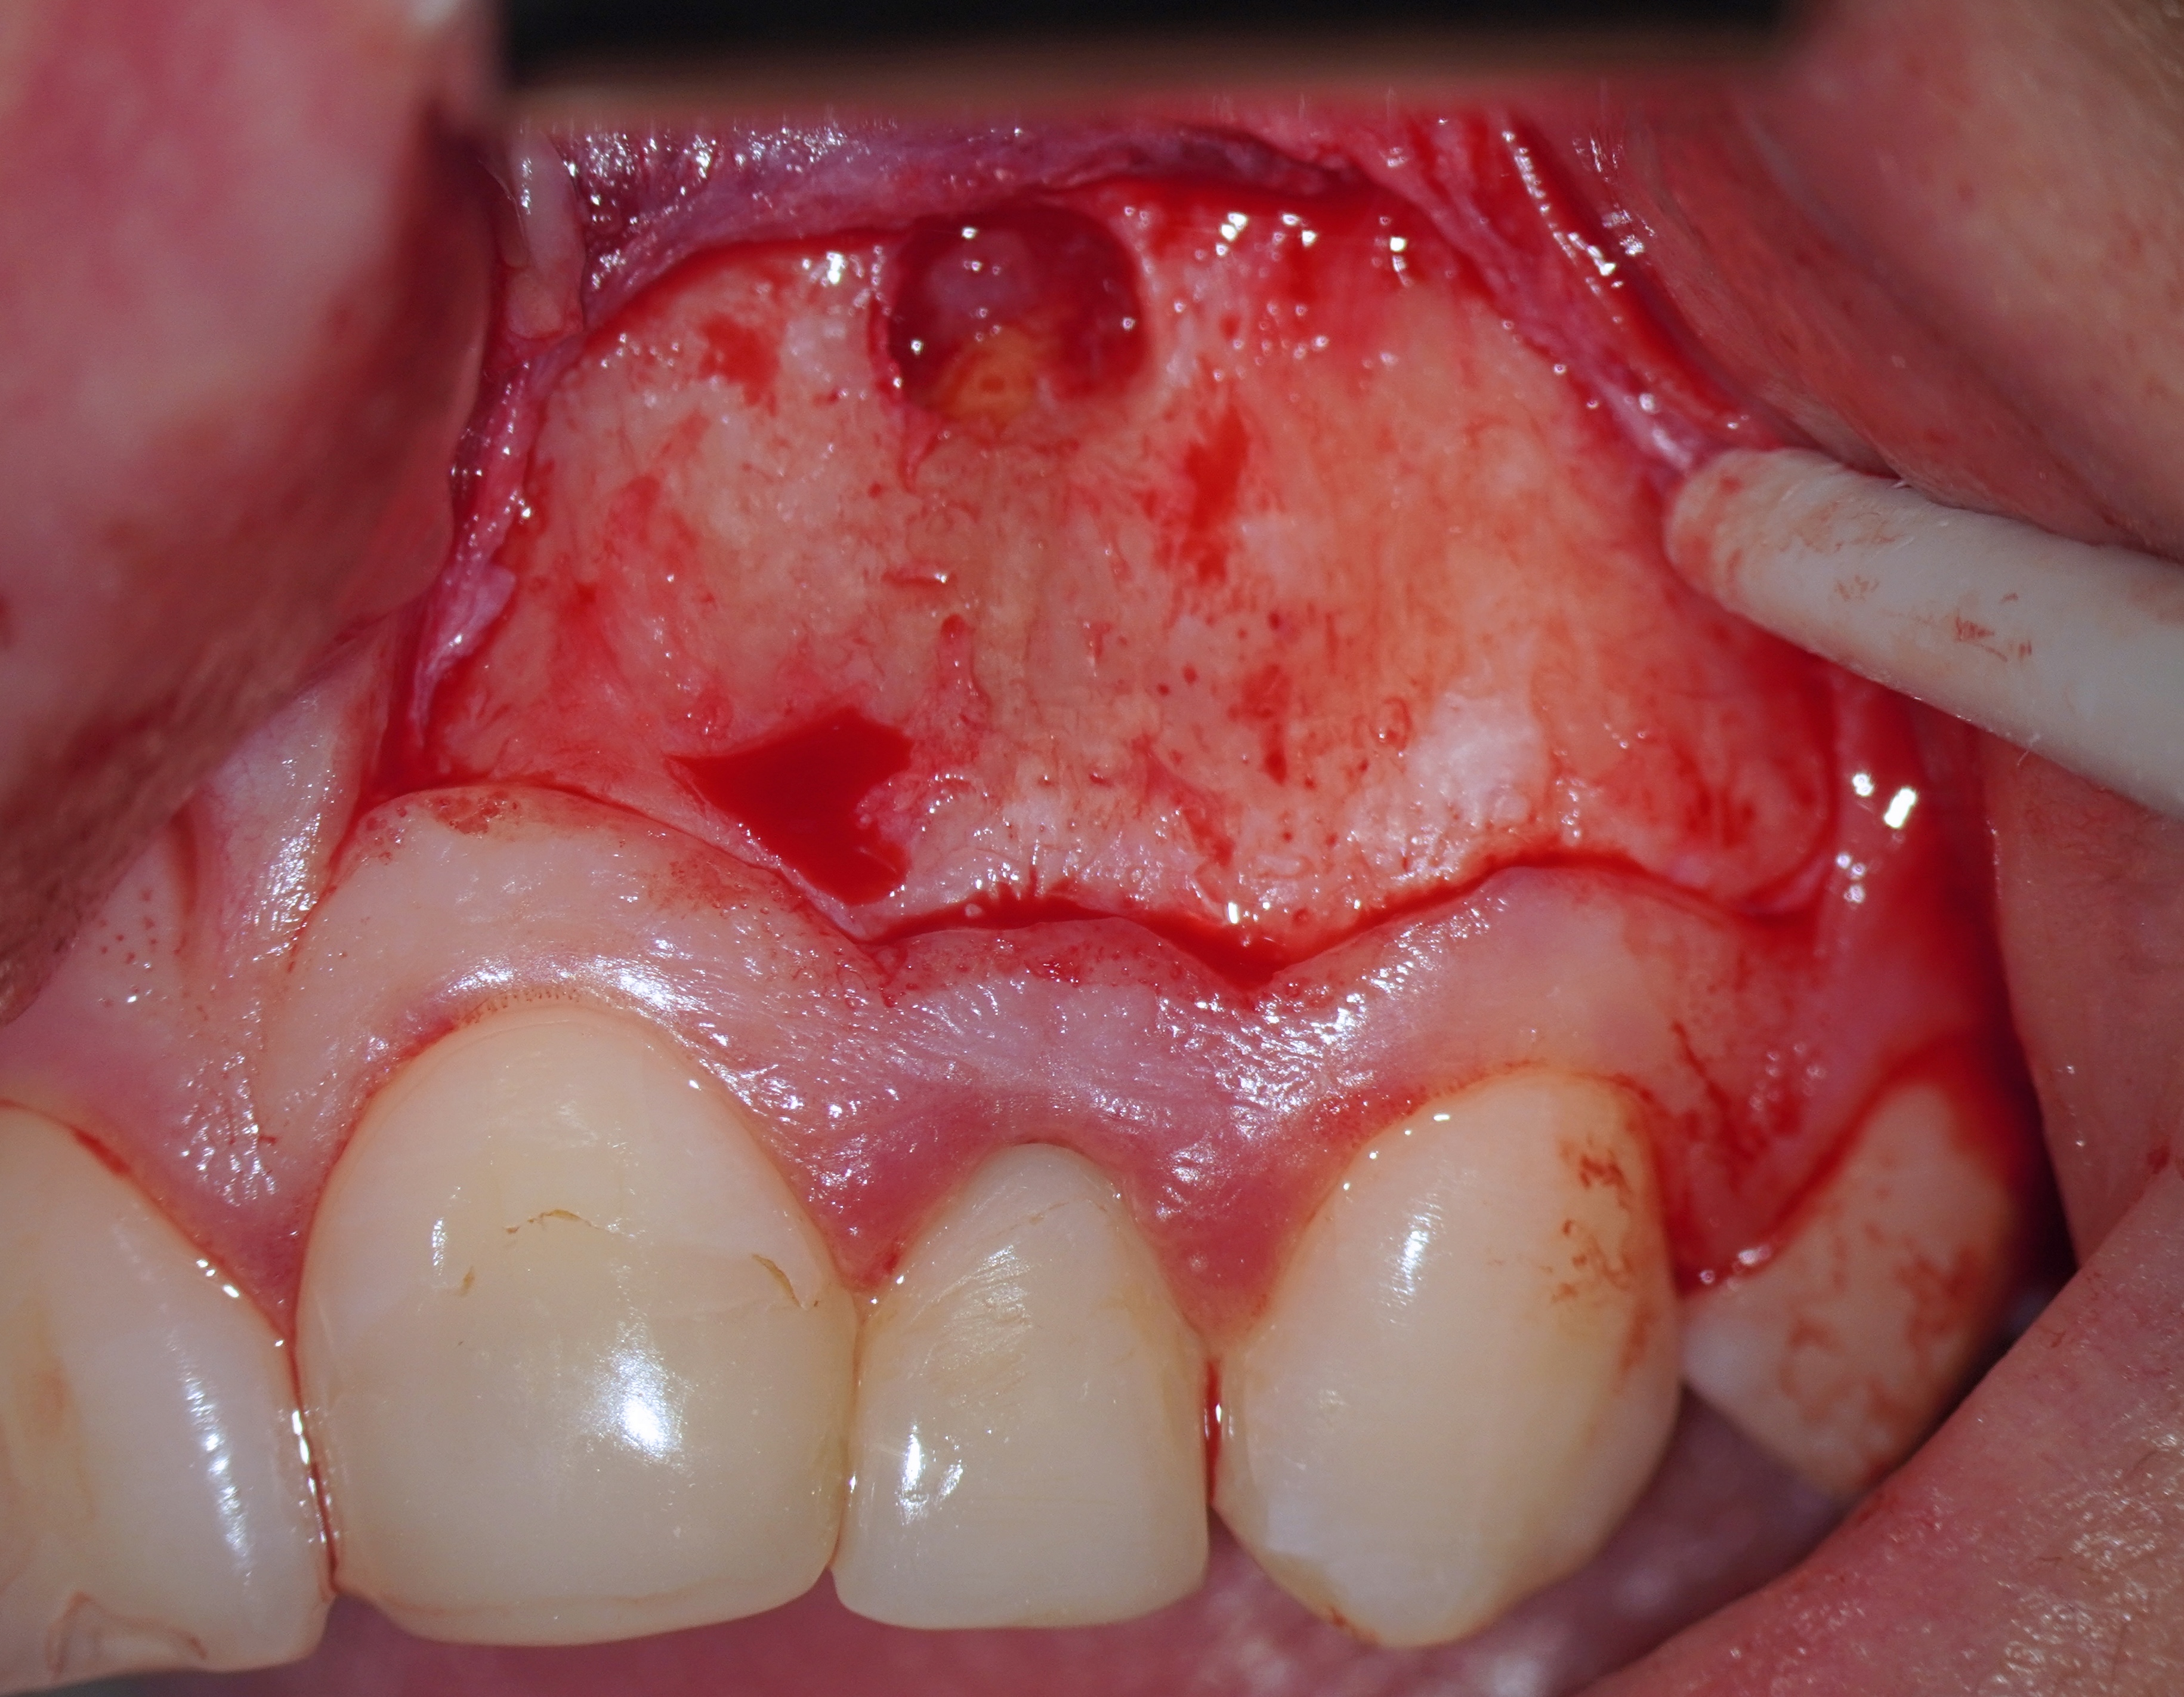

One of the postulates of “The golden rules of the flap design” reads, “The incision must never cross a bone defect. Incisions should be made away from the lesion if possible” [29]. More recent research also supports this view “The underlying apical lesion or surgical bony access must not extend to the flap margins” [16]. Using CBCT, the surgeon can accurately measure the size of the bone defect and plan the incision design so that the incision is at a distance from the bone defect (or the area where the osteotomy will be performed). If the surgery is not planned carefully and the incision passes through a bone defect, the risk of complications associated with healing increases significantly. There is the risk of postoperative infection [12]. These complications are sometimes observed (Fig 6).

Therefore, the selection of this type of incision requires thorough treatment planning [12]. To avoid the incision falling into an existing bone defect or a defect created by an osteotomy, it is rational to plan a submarginal incision. We can determine whether we can make it, according to the clinical situation of a patient by following approach. To do this, first we need to determine on the CBCT where the bone defect is located or where the osteotomy will take place. Then, using a virtual ruler, measure the distance from the incisal edge of the tooth on which the intervention will be performed to the beginning of the bone defect or osteotomy (Fig 7).